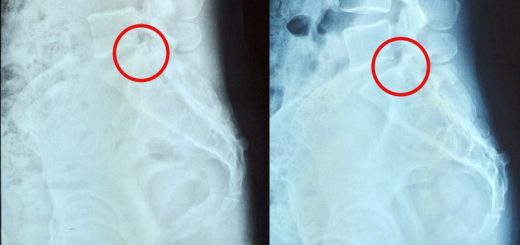

Weak Lower Extremities Due To Lumbar Disc Degeneration

Lumbar nerve compression leading to Cold Extremities